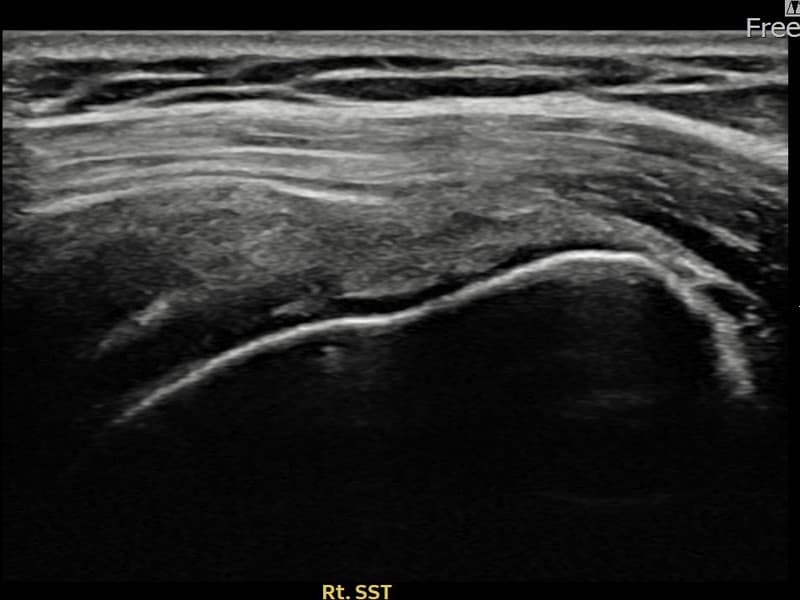

施術後

術前超音波にて右 棘上筋腱 関節面側部分断裂・右肩棘上筋腱のエコー不連続と腱欠損(12mm × 4mm (腱厚の約48%欠損))を確認。術後超音波では断裂部位が再生組織で充填され、腱の連続性回復とエコーパターンの正常化が確認されました。